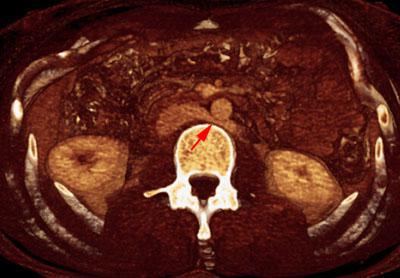

Trombosis de la vena renal izquierda